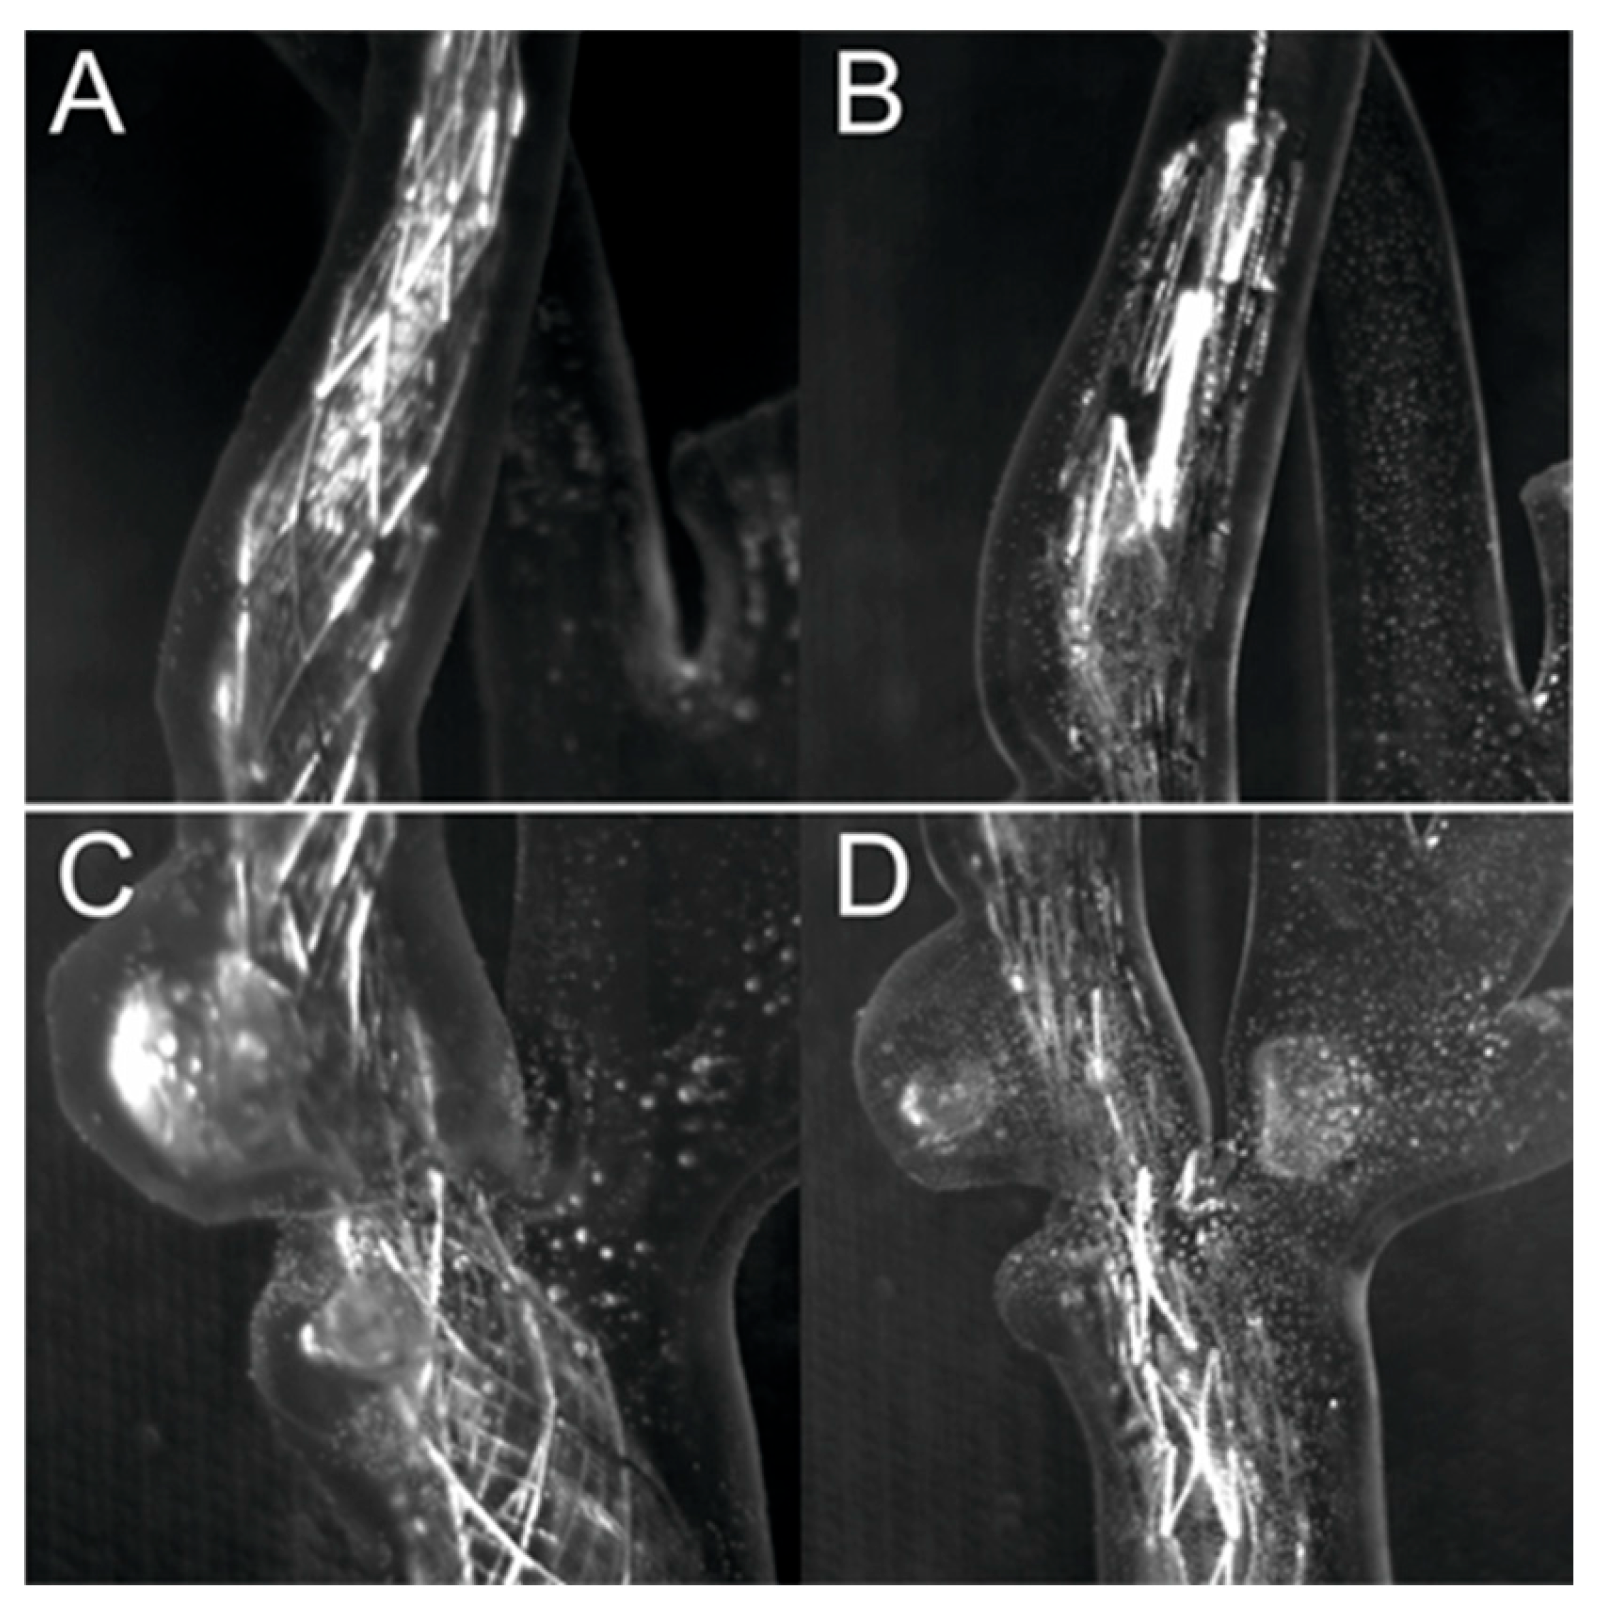

3.2. Percutaneous Carotid Artery Stenting on 3D-Printed Phantoms